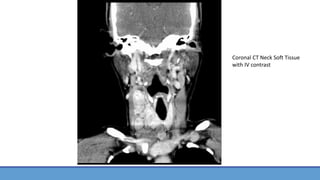

Coronal CT Neck Soft Tissue

with IV contrast

• CT Neck Soft Tissue w/ IV Contrast had been performed in ED prior to admission and ENT consult